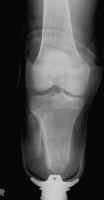

Immediate post-operative films of a good BKA. Stump-shrinking cast and skin staples

are present.